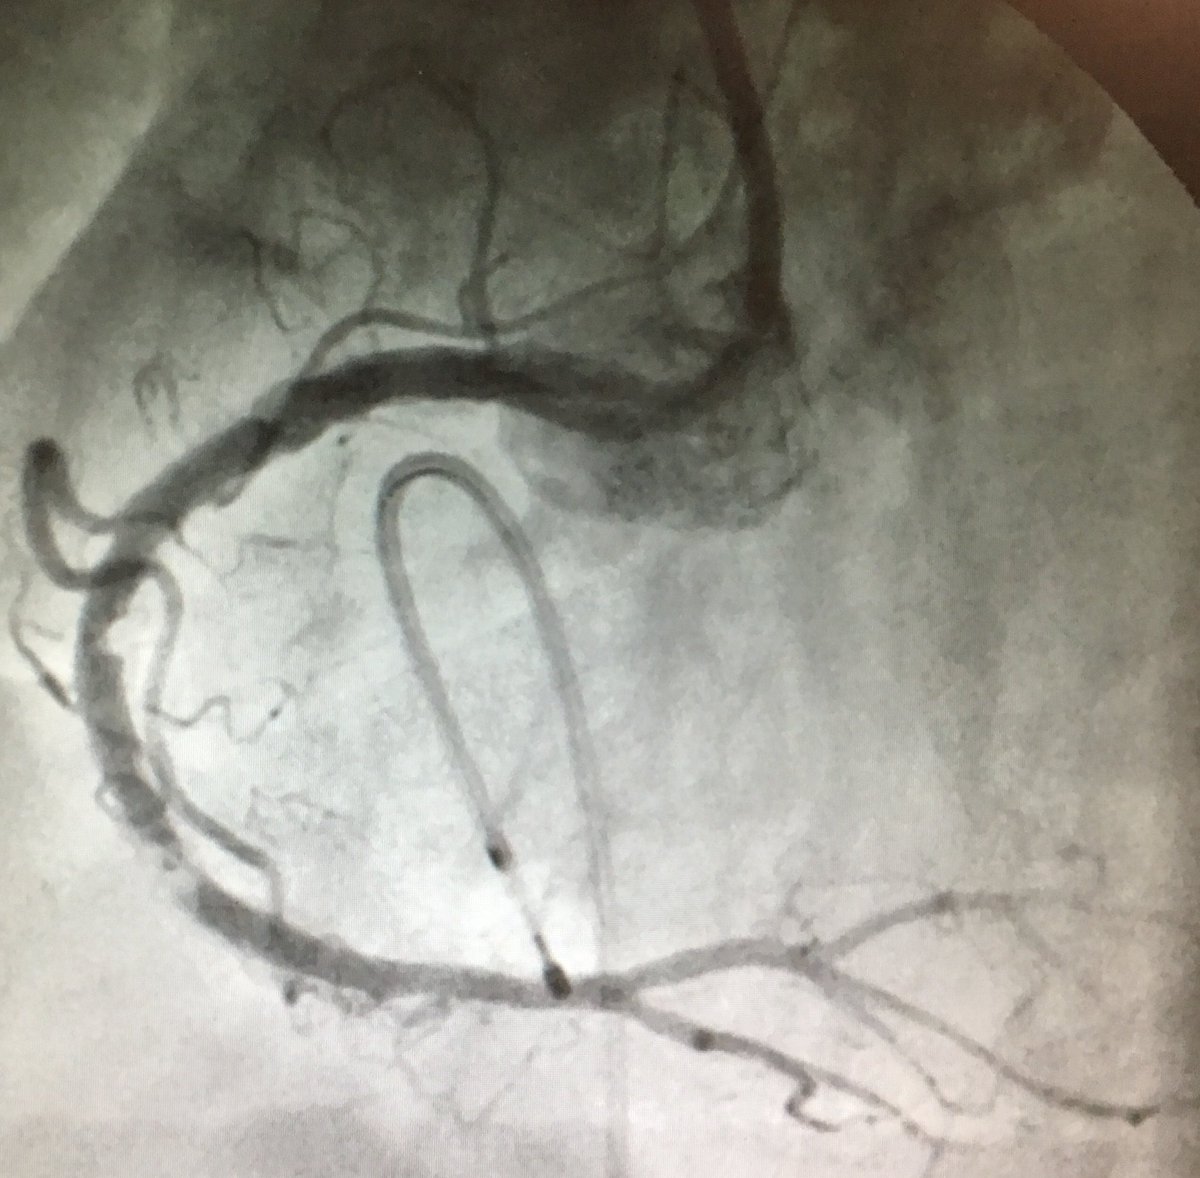

#Rotablation #Angioplasty: A great pleasure doing #Rotablation with the Great #Teacher Dr #Godin. Rotablation uses a tiny drill with a #diamond-tipped burr, powered by compressed air to break up calcified plaque (hard block) that is clogging the coronary artery. Breaking up

A great pleasure doing #Rotablation with the Great #Teacher Dr #Godin.

Rotablation uses a tiny drill with a #diamond-tipped burr, powered by compressed air to break up calcified plaque (hard block) that is clogging the coronary artery.